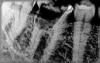

Secretive Опубликовано 28 декабря, 2012 Поделиться Опубликовано 28 декабря, 2012 снимки прелогаю,про поломанный инструмент знаю.пациент 56 года рождения,пациент обратился с жалобами на постоянный привкус кислого и незначительную болезненность десны в области 1.6 зубапри осмотре на 1.6 и 1.7 зубах штамповки подлежащие замене,решено было заменить не только их но и на 2.6 2.7 и 3.6 зубах.1.6 пришлось удалить так как там была "каша" c остальными проблем не возникло кроме виновника темы.идет уже 3 месяц,зуб под мк коронкой,жалоб нет,в начале января пригласил сделать снимок,вот хотелось бы узнать ваше мнение уважаемые коллеги. Ссылка на комментарий

Secretive Опубликовано 28 декабря, 2012 Автор Поделиться Опубликовано 28 декабря, 2012 заапикальное рассмотрим когда он придет на осмотр и снимок,выложу снимки сюда,на снимках в некоторых проекциях кажется что фуркация есть но все нормально,стенки смотрел ортопед и сказал что удов.и что ни стекловолоконных штифтов ни вкладку не надо все будет и так стоять!нет полость выше уровня,насчет пришейка не знаю,ну думаю январский снимок все прояснит,и еще по поводу 5-го канала где крючок,у меня сомнения по нему я границ ничего не вижу после контроля я был уверен что вогнал гутту в периодонт,смотрели коллеги утверждают что все норм,объясняют это тем что зуб был под формалином 25 лет. Ссылка на комментарий

Afffinity Опубликовано 29 декабря, 2012 Поделиться Опубликовано 29 декабря, 2012 +1. Особенно на предпоследнем снимке хорошо видно, что от фуркации мало что осталось. Зуб на вылет изначально был. Ссылка на комментарий

Л Ю С Я Опубликовано 29 декабря, 2012 Поделиться Опубликовано 29 декабря, 2012 Мне кажется там не 5 к.к,а меньше средняя гутта в перфорации,и которая левее ,типа в дистальном,но может я ошибаюсь,надо, конечно, смотреть в ПР,но похоже в бифуркации там каша,либо очень тонко.Даже если восстановите будет фрактура в течении 6 мес-2 лет,откроется свищ.Вы работаете с апекслокатором?Везде он показывал,что Вы в канале?Я бы удалила. Ссылка на комментарий

sorriso Опубликовано 29 декабря, 2012 Поделиться Опубликовано 29 декабря, 2012 Чтобы убедиться в удалении,сделайте КТ,посмотрите что там и к чему! А ваш "5 канал" и 4-й,который в фуркации-явно перфорации! Ссылка на комментарий

Secretive Опубликовано 29 декабря, 2012 Автор Поделиться Опубликовано 29 декабря, 2012 Мне кажется там не 5 к.к,а меньше средняя гутта в перфорации,и которая левее ,типа в дистальном,но может я ошибаюсь,надо, конечно, смотреть в ПР,но похоже в бифуркации там каша,либо очень тонко.Даже если восстановите будет фрактура в течении 6 мес-2 лет,откроется свищ.Вы работаете с апекслокатором?Везде он показывал,что Вы в канале?Я бы удалила.каши небыло,небольшое перфо было,закрыл триоксидентом,апекслокатором работаю у меня фирмы dentsply propex 2,в каналах с такими изменениями он мало чего показывал, Ссылка на комментарий

Secretive Опубликовано 29 декабря, 2012 Автор Поделиться Опубликовано 29 декабря, 2012 Чтобы убедиться в удалении,сделайте КТ,посмотрите что там и к чему! А ваш "5 канал" и 4-й,который в фуркации-явно перфорации!4-й который в фуркации это дист.вот только не помню какой,и который левее тоже,у меня сомнения по 5-му каналу где гутта крючком завернулась,просто снимок с такой проекцией получился. 1 Ссылка на комментарий

baddario Опубликовано 30 декабря, 2012 Поделиться Опубликовано 30 декабря, 2012 4-й который в фуркации это дист.вот только не помню какой,и который левее тоже,у меня сомнения по 5-му каналу где гутта крючком завернулась,просто снимок с такой проекцией получился.Уважаемый Secretive,судя по вашим снимкам зуб был на вынос сразу, вы только усугубили прогноз для последующей имплантации, у вас мин 2 перфы по фуркации и одна апикальная в дистальной системе, для нормального функционирования протетики необходимо 2мм феррула. ИМХО. Кстати Док невижу ваш раббер? Ссылка на комментарий